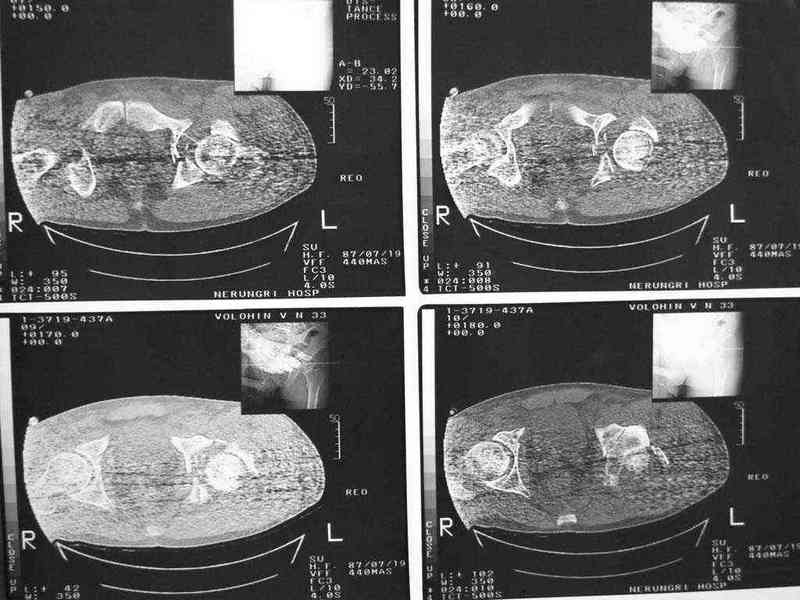

Уважаемые коллеги, нужна помощь, поступил больной с переломом лонной и седалищной кости слева, перелом вертлужной впадины слева, нестабильный вывих левой бедренной кости. Попытки вправить бедренную кость- безуспешны. На данный момент находится на скелетном вытяжении, посоветуйте какую тактику ведения данного больного выбрать оптимально.Спасибо.

еще одно дополнение